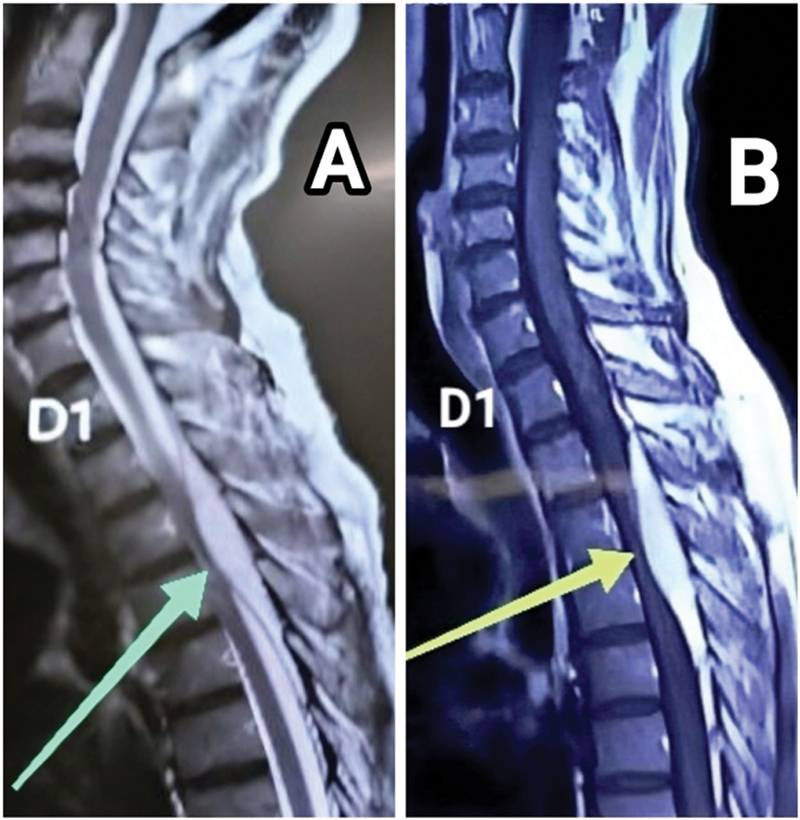

Spinal extradural angiolipomas (SEALs) are rare, benign neoplasms composed of mature adipocytes and vascular elements. They are often noninfiltrating and located in the posterior aspect of the spinal canal at the level of thoracic/dorsal vertebrae. Back pain, progressive paraparesis, and sensory disturbance in lower limbs are the typical symptoms. Here, we discuss two cases of SEALs presenting with subacute paraparesis. The magnetic resonance imaging of one patient was reported to be suggestive of spinal metastasis/plasmacytoma/sarcoma, while the other was reported as a spinal extradural hematoma. After laminectomy, both lesions were recognized as encapsulated extradural tumors and en-bloc resection was done. Postoperatively, the neurological deficits improved and there was no recurrence on 2-year follow-up. Histopathology characterized both of them to be extradural angiolipomas. Current experience and literature support curative surgical resection as the gold standard. The prognosis is excellent in most cases, even if total resection is not feasible. It is due to the slow-growing nature of the tumor and absence of malignant transformation.